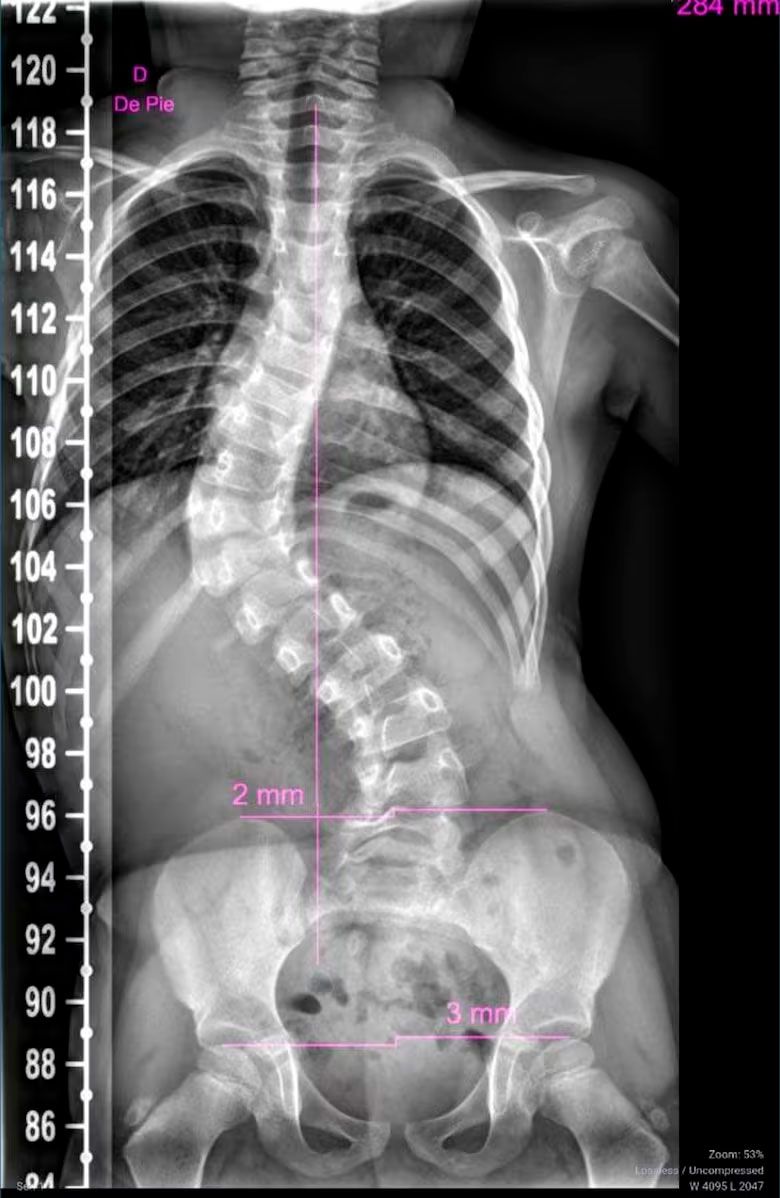

Pilar tiene 3 años y medio, pero su vida está marcada por un calendario médico sin pausas. Cuatro a cinco veces por semana asiste a distintos tratamientos de rehabilitación. Su madre, María Martín, repite los números como una sentencia: escoliosis de 78 grados. "Una de 50 ya se considera grave", explica angustiada. La razón de esta deformación está en un pinchazo que recibió el 6 de junio de 2022, cuando tenía apenas días de vida, en el Hospital Materno Neonatal de Córdoba. Ese día, la enfermera Brenda Agüero le inyectó potasio en la espalda.

"Ese pinchazo de potasio le provocó una necrosis en el músculo de la espalda; no tiene esa parte que es la que ayudaría a que su columna crezca derecha", contó María a La Nación. La pequeña es la única de los sobrevivientes que conserva la marca visible del ataque: un hematoma en la espalda que fue considerado prueba clave durante el juicio oral.

Hace una semana, los médicos del Hospital de Niños le comunicaron a María un diagnóstico devastador. "Tienen que enyesarle la parte superior e ir cambiando el yeso cada tres meses. Eso hasta que se la pueda operar", relata. La cirugía no es recomendable aún por la edad de la niña. El tratamiento implicará colocarle un yeso que dejará un hueco en la zona abdominal para que pueda alimentarse. No podrá bañarse normalmente. Y cuando tenga edad suficiente, enfrentará varias cirugías a lo largo de su vida.

Ya pasó por una operación anterior, cuando la cicatrización se había adherido a una costilla. "Va a rehabilitación desde siempre, pero al no tener ese lado del músculo, la columna se tuerce", insiste María, quien también es madre de una adolescente de 15 años y de una beba de 8 meses.